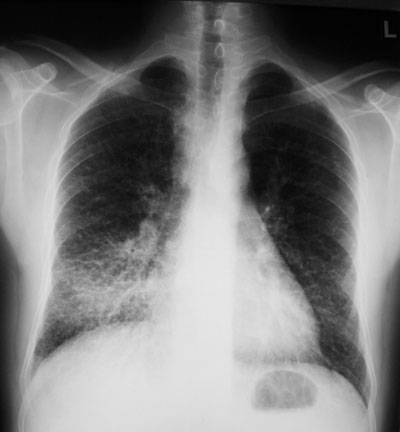

Ein 46-jähriger Patient konsultiert Sie wegen chronischem trockenem Husten seit zwei Monaten und einem Gewichtsverlust von 6 kg in derselben Zeit.

Dyspnoe verspürt er lediglich bei starker Anstrengung. Fieber wird verneint. Lungenperkussion und -auskultation sind unauffällig; im Gegensatz zum Röntgenbild:

Wie würden Sie den Befund beschreiben?

Welche beiden folgenden Differentialdiagnosen sind aufgrund der Klinik und des radiologischen Befundes am wahrscheinlichsten?